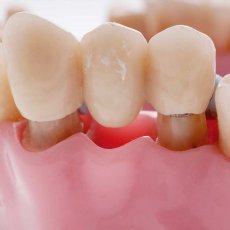

假牙的製作將分三次,首先將植體接出,並製作臨時假牙.接下來印模,製作正式牙冠.最後試戴牙冠並完成.